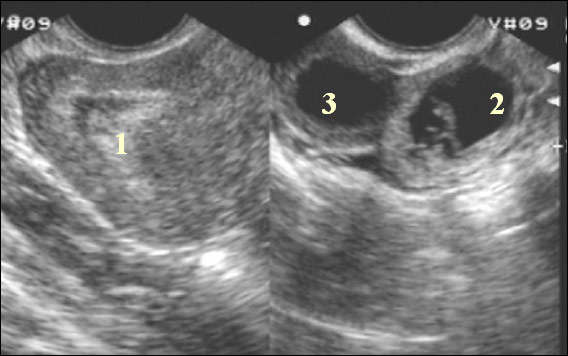

Что это означает? Гравидарный эндометрий можно выявить во время ультразвукового исследования. Он отличается по эхогенности от неизмененного, что позволяет хорошо его визуализировать в процессе процедуры. Его можно обнаружить как при трансабдоминальном, так и при трансвагинальном УЗИ. В заключении врача и в описании результатов УЗИ данное состояние может быть также обозначено как гравидарная реакция эндометрия.

Как уже упоминалось ранее, данное состояние выявляется с помощью ультразвукового исследования. Оба метода — трансвагинальное и трансабдоминальное — являются эффективными, однако информативность второго немного ниже. Поэтому, если требуется точно оценить изменения в слизистой оболочке, предпочтительнее использовать трансабдоминальный подход. Даже при задержке всего в один день изменения могут быть заметны и четко различимы. На 5-8 день задержки обычно уже можно определить, есть ли плодное яйцо, то есть выяснить, продолжается ли беременность или произошел выкидыш на ранних сроках.

Признаки гравидарного эндометрия могут включать утолщение слизистой оболочки матки, увеличение кровоснабжения и изменение структуры клеток. Эти изменения могут быть выявлены с помощью ультразвукового исследования, которое показывает характерные признаки беременности, такие как наличие желточного мешка или эмбриона в полости матки.